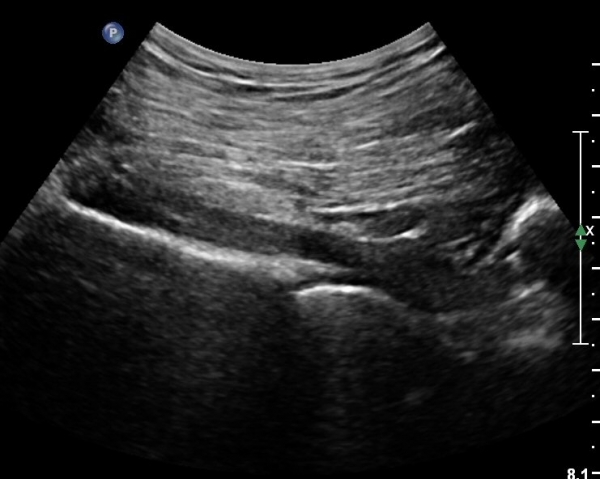

ŽÃËÀÚ¸¦ ´ëÀüÀÚ°¡ º¸À̵µ·Ï ¿ÜÃøÀ¸·Î À̵¿Çϸé Á°ñÇ¥Ãþ¿¡ ´ëÀüÀÚ·Î ÁÖÇàÇÏ´Â ÀÛÀº ³×°³ÀÇ ±ÙÀ°ÃþÀÌ °üÂûµÇ´Âµ¥ ¸Ó¸®ÂÊ¿¡¼­ ¾Æ·¡·Î SG, OI, IG, QF¸¦ °üÂûÇÒ ¼ö ÀÖ°í, ÀÌ ±ÙÀ°µé Ç¥Ãþ¿¡¼­ °í¿¡ÄÚ·Î °üÂûµÇ´Â Ÿ¿øÇü ±¸Á¶¹°ÀÌ Á°ñ½Å°æÀÌ´Ù(»çÁø 4, 5, 6, 7).